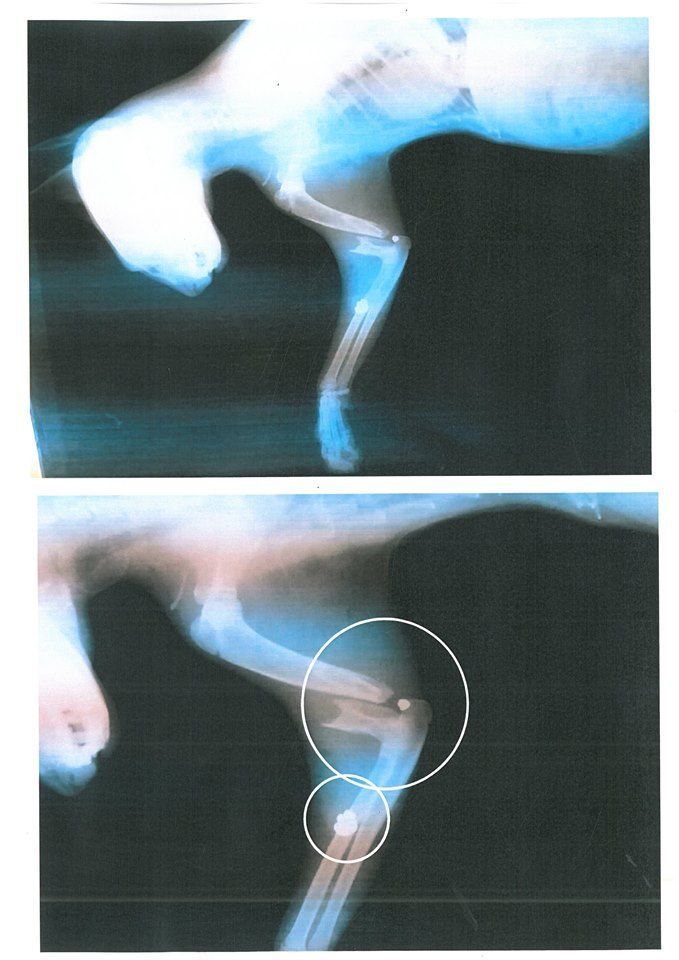

Στην Κερατέα της Αττικής επί της οδού Αγίας Παρασκευής η Ειρήνη Καλυβιώτη εντόπισε στις 25 Φεβρουαρίου ένα τραυματισμένο γατάκι που κυριολεκτικά σύρθηκε μέχρι το μαγαζί της και έτσι η γυναίκα, η οποία είδε το ζώο με διαλυμένο πόδι το μετέφερε σε κτηνιατρείο του Γιώργου Λυγιά και της Σκεύης Νεοφύτου. Εκεί διαπιστώθηκε ότι το γατάκι έχει πυροβοληθεί με αεροβόλο και το πόδι του ίσως ακρωτηριαστεί...

Η κα Καλυβιώτη γι' αυτό το έγκλημα επισημαίνει τα εξής: «Την προσοχή σας παρακαλώ, κάτοικοι και επαγγελματίες της κεντρικής πλατείας Κερατέας και γύρω δρόμων. Χτες οδήγησα γατάκι στο κτηνιατρείο το οποίο... ΠΥΡΟΒΟΛΗΘΗΚΕ από ΑΕΡΟΒΟΛΟ. Αρκετά αδέσποτα γατάκια που σίτιζα το τελευταίο διάστημα έχουν χαθεί χωρίς να έχω βρει πτώμα. Το πόδι του συγκεκριμένου ζώου που ήρθε στο μαγαζί μου ζητώντας βοήθεια, αχρηστεύθηκε.